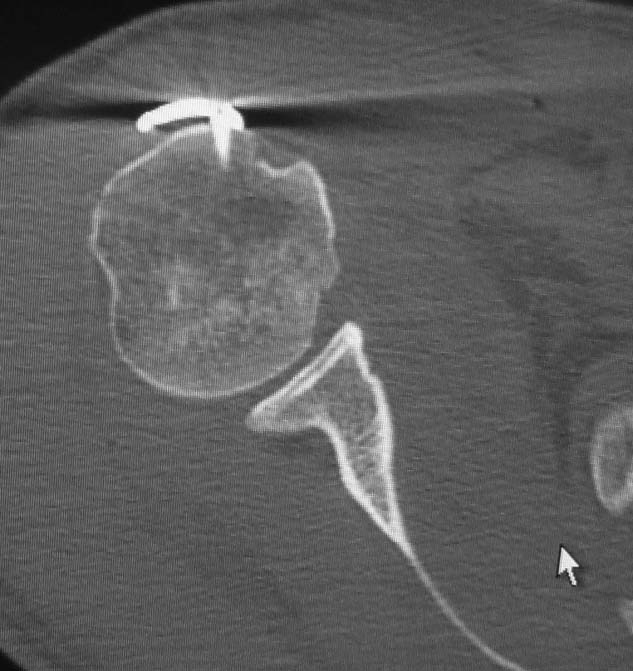

Уважаемые коллеги. Уже в давно в нашей клинике стараемся практически при всех переломах выполнять КТ. Находки, радикально меняющие тактику дальнейшего лечения, встречаются очень часто. Позвольте поделиться очередной такой находкой. С подобным сочетанием раньше встречаться не доводилось. Пациент 44 лет. На рентгенограммах простой перелом диафиза плечевой кости. Выявленный на КТ вдавленный перелом головки по рентгенограммам нельзя было заподозрить даже ретроспективно, после выполнения КТ.Наряду с остеосинтезом диафиза выполнена репозиция вдавленного перелома головки через отверстие в малом бугорке (обозначено стрелкой). Сформировавшаяся после репозиции полость заполнена аутостружкой с крыла подвздошной кости.

Возможность осмотра места перелома достигнута путем рассечения сухожилия подлопаточной мышцы. Отверстие в малом бугорке проделано 5мм сверлом. Через отверстие под вдавленный фрагмент подведен маленький периостальный элеватор. Под непосредственным визуальным контролем фрагмент вытолкнут на место. Образовавшаяся полость заполнена костной аутостружкой.

Вдавленный перелом переднего отдела головки плеча - повреждение Маклафлина или обратный Хилл-Сакс. Это результат самопроизвольно устранившегося заднего вывиха плеча. Сочетается с повреждением хрящевой губы и капсулы в заднем отделе плечевого сустава - обратный Банкарт. КТ, пожалуй, единственный способ диагностики. Возможны и костные повреждения заднего края гленоида. Было бы интересно взгянуть на КТ реконструкцию гленоида.